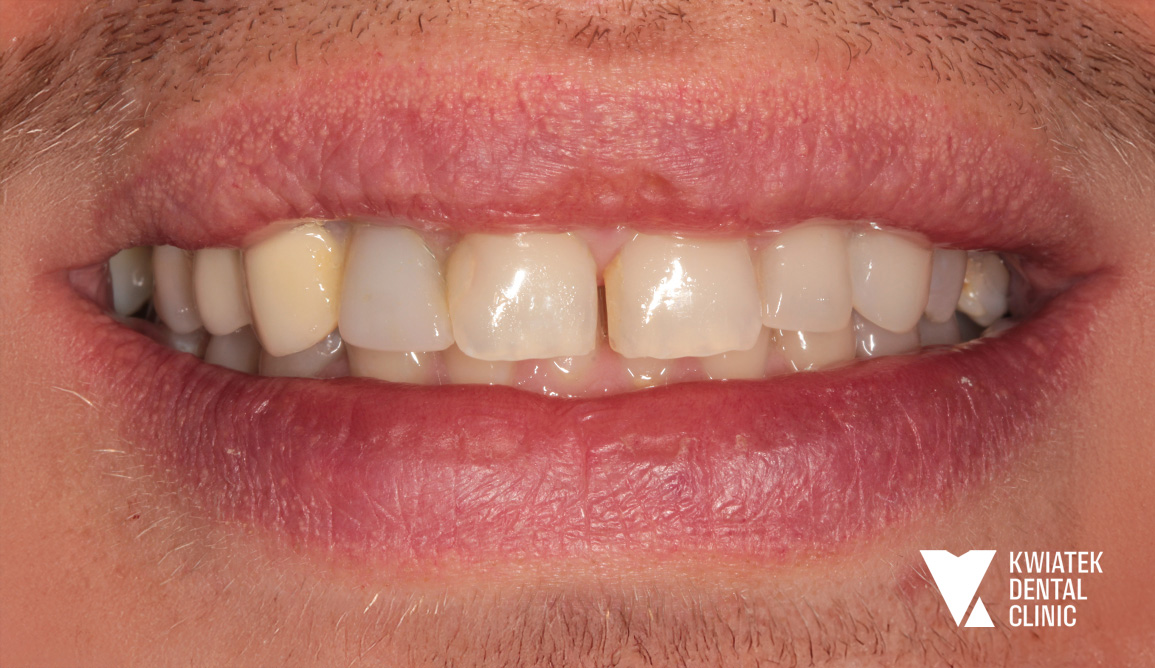

Pełna rekonstrukcja zwarcia i estetyki - historia wymagającej metamorfozy

Pacjent zgłosił się do kliniki z zaawansowanymi problemami stomatologicznymi: licznymi ubytkami próchnicowymi, brakami zębowymi, starciem zębów oraz zaburzeniami zwarcia. Leczenie obejmowało kompleksową diagnostykę, leczenie zachowawcze i endodontyczne, zabiegi chirurgiczne, implantację oraz wieloetapową odbudowę protetyczną. Efektem terapii jest perfekcyjnie zbalansowany zgryz, najwyższy komfort funkcjonowania oraz naturalnie piękny uśmiech, który podkreśla indywidualny charakter pacjenta i pozwala mu w pełni cieszyć się nim każdego dnia.